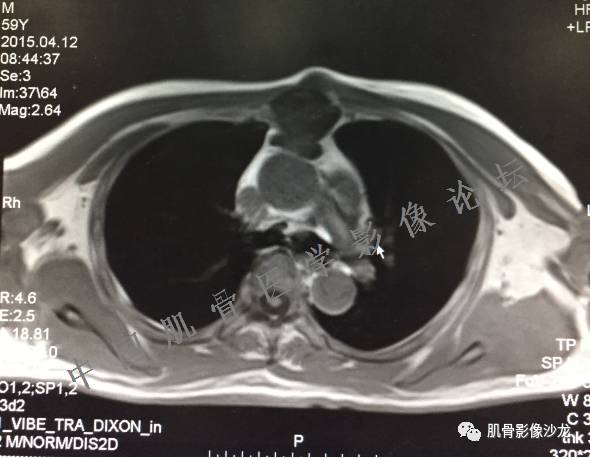

雪舞 :第二例,位于骶骨,有骨质破坏并有软组织肿块,软组织肿块边界清

雪舞: 第二例我们能够看到破坏与软组织肿块不成比例,软组织肿块大,破坏小

雪舞 :第二例挺难的,骨质破坏是溶骨性的,局部皮质中断,软组织肿块外缘光滑